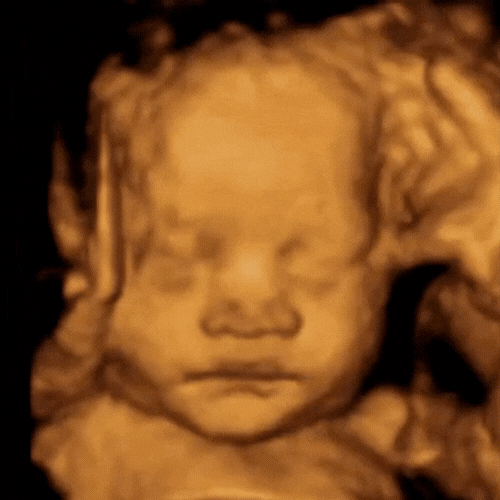

Our state-of-the-art technology (GE Voluson Swift) is one of the most popular ultrasound machines for obstetric scanning. It features class leading 4D imaging as well as proprietary GE efficiency technologies. 3D/4D imaging modes, CrossXBeam and Speckle Reduction imaging assist with excellent accuracy.

ScanSanctuary Client Scan Examples